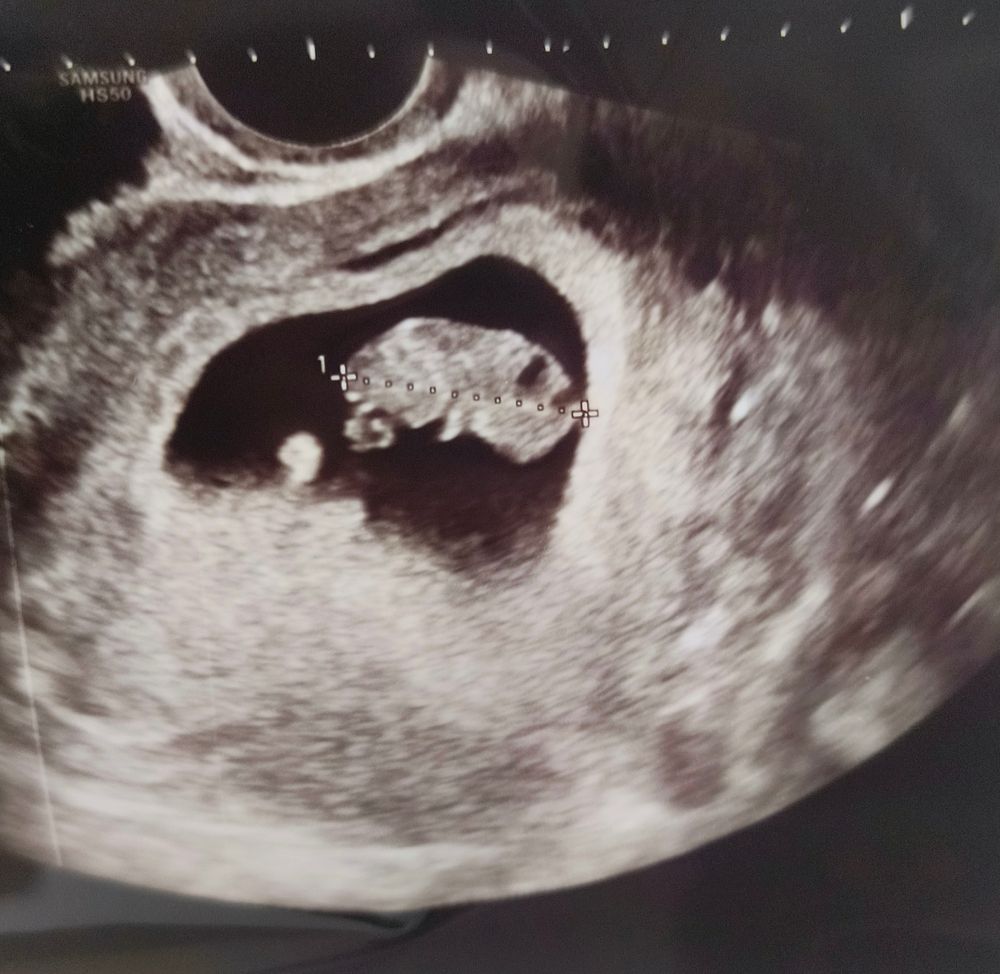

жду девочку, 13 неделя Москва

9+3

Всё в порядке 10+3